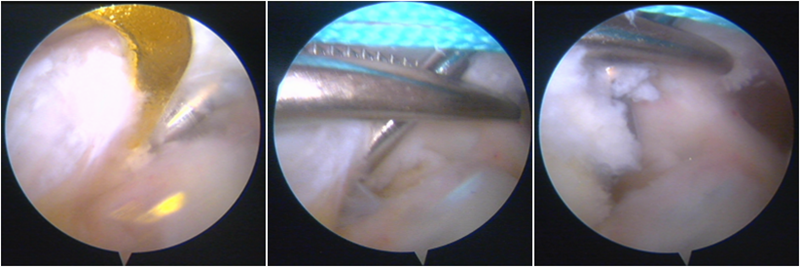

镜下显示ACL残束

内侧半月板

外侧半月板

股骨侧保残骨道建立

股骨侧骨道建立,椭圆形扩孔保残9mm

韧带导入过程

送止血带后韧带表明血管膜